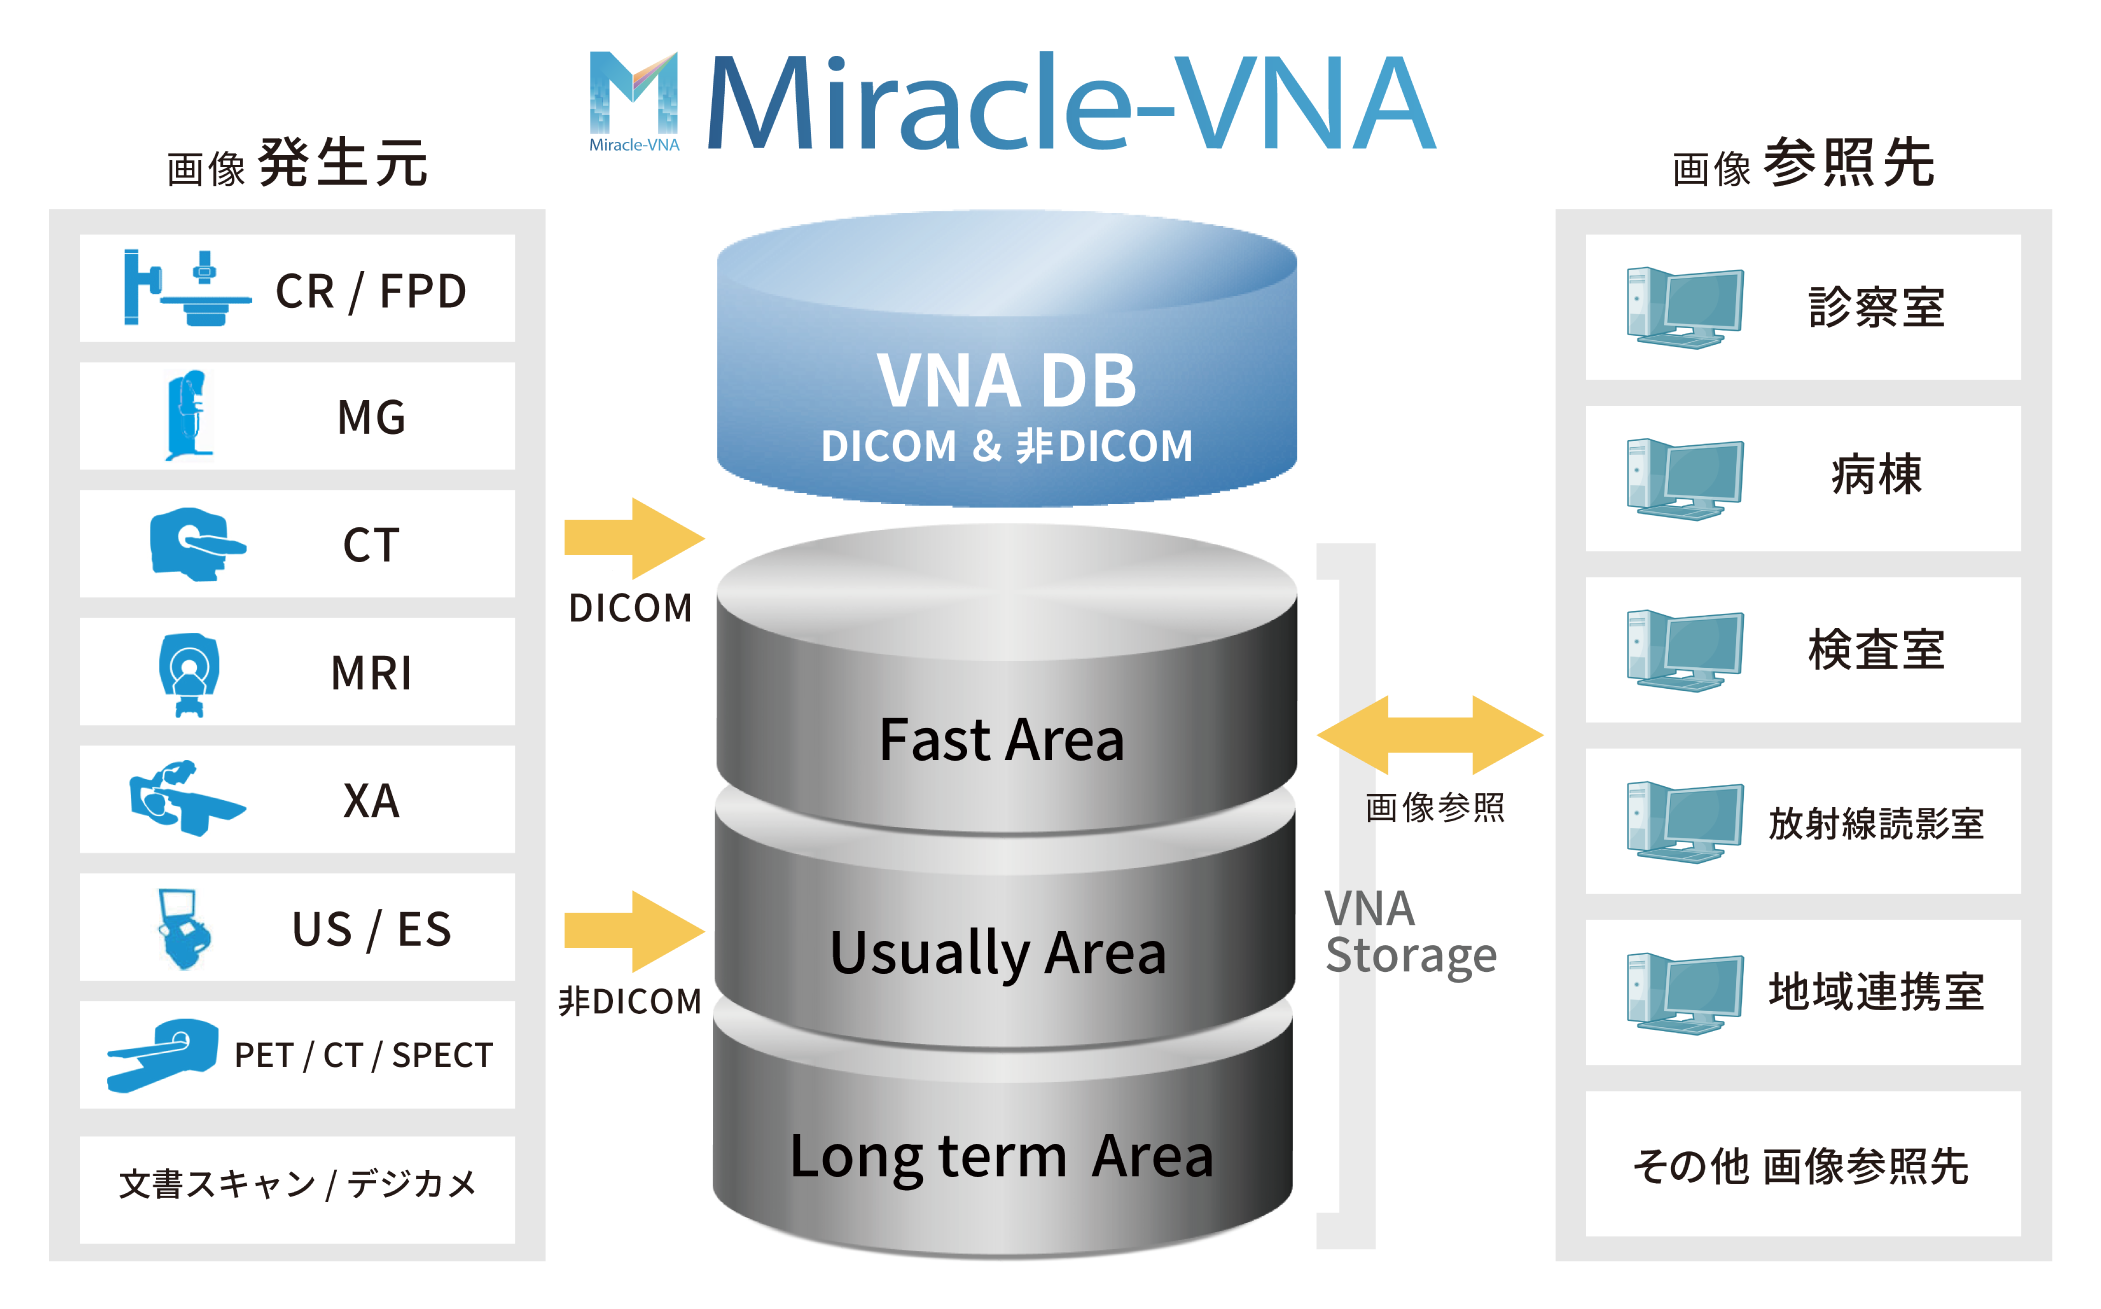

オープン型医用画像データ

一元管理システム Miracle-VNA

DICOM/非DICOMデータを一元管理

DICOM/非DICOMデータを一元管理

DICOMだけでなく、非DICOMデータや他の標準フォーマットもサポート。

異なるPACSやEMRシステムとシームレスに連携できる機能で、互換性を最大限確保します。

基本パッケージのコストを最小限に抑え、データベースの一元化によって効率的なストレージ構成を組んだ最先端のシステムをご提供いたします。

アーカイブ3層構造

アーカイブ3層構造

画像参照頻度を考慮し、ストレージ構造を高速・中速・低速とした3層データ管理を実現。

高価な高速ストレージの使用を最小限に抑え、全体的なストレージコストを効率的に管理しながら、必要なデータに迅速にアクセスできる環境を構築いたします。

システム概要図